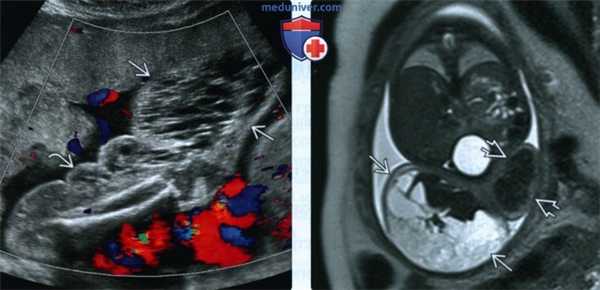

(Слева) УЗИ плода с СКТВ. Визуализируется многокамерное инфильтрирующее кистозное образование бедра и голени. Образование преимущественно аваскулярное и имеет кистозную структуру.

(Справа) МРТ голени, поперечный срез. Происхождение образования, окружающего мышцы, неочевидно. В данном случае образование не распространяется в глубь туловища. Стрелками отмечена пораженная голень, - здоровая.

2. УЗИ при синдроме Клиппеля-Треноне-Вебера у плода:

• Кистозное образование нижней конечности, локализующееся подкожно:

о Многокамерная киста:

- Кисты локализуются вокруг бедренной, большеберцовой и малоберцовой костей

- Соотношение эхогенности кистозно-измененных и мягких тканей варьирует:

Зависит от степени гипертрофии мягких тканей, выраженности поражений лимфатических и кровеносных сосудов

о Васкуляризация, по данным ЦДК, варьирует:

- Чаще находят снижение васкуляризации, чем усиление:

Интенсивная васкуляризация чаще становится причиной сердечной недостаточности

- Возможна персистенция эмбриональной латеральной маргинальной вены:

Крупная вена, проходящая от боковой поверхности голени к боковой поверхности стопы

- Могут определяться флеболиты:

Венозные кальцинаты

Гиперэхогенные очаги в подкожной жировой клетчатке